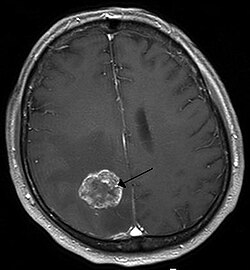

Beyin xərçənginin MRTdə görüntüsü

28 yaşlı kişidə MRT ilə üzə çıxarılan beyin şişi

Məcburi müayinə üsullarına tendon reflekslərinin fəaliyyətinin təyin edilməsi, toxunma və ağrı həssaslığının yoxlanılması daxildir. Diaqnostik tədbirlər xəstənin şikayətlərindən asılı olaraq və differensial diaqnostika məqsədilə genişləndirilə bilər. Beləliklə, məsələn, xəstə koordinasiya çatışmazlığını qeyd edərsə, barmaqdan buruna test aparılmalıdır, Romberg mövqeyində sabitliyi yoxlayın. Beyin şişindən şübhələnirsinizsə, xəstə kompüter tomoqrafiyasına (CT) və ya maqnit rezonans tomoqrafiyasına (MRT) göndərilir. Kontrastlı MRT beyin şişlərinin diaqnostikasında "qızıl standart"dır . Tomoqrammada həcmli formalaşma aşkar edilərsə, xəstənin ixtisaslaşdırılmış xəstəxanada xəstəxanaya yerləşdirilməsi məsələsi həll edilir.